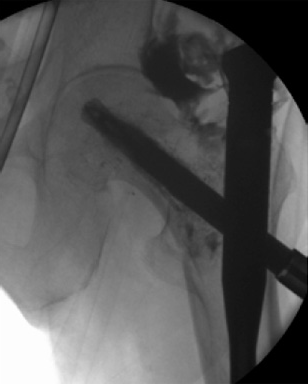

After finishing the usual procedure of inserting the nail and the perforated blade, a leakage into the joint has to be excluded by injection of contrast medium through the perforated blade first. Then the prefilled side opening cannula is inserted into the blade and the position checked by image intensifier. A medial perforation must be avoided. Furthermore, the special 1 ml syringe is adapted to the cannula (Fig 6) and the cement can be injected (Fig 7). By turning the cannula the positioning of the cement around the helical blade can be navigated. Around 36 ml of cement should be injected. The whole injection procedure must be done under image intensifier control.

An 82-year-old woman with an unstable pertrochanteric fracture of the right proximal femur. Her Barthel Index was 80 and her preoperative Parker mobility score was 5, which means that she was walking at home unassisted. The patient's preoperative Parker mobility score of 5 was reached again at the 3-month follow-up.